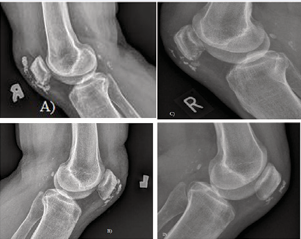

Rodnan skin scor was 7/51. X rays (knee/elbow/hand) showed diffuse subcutaneous calcification (Figure 2).

Figure 2 X-rays of knees (A, B), left elbow (C) and hands (D) showed diffuse subcutaneous calcification.

functional improvement and partial radiographic regression of calcinosis (Figure 5).

![Radiographic aspect of the knee [right (A) and left (B)] before and after [right knee (C) and left knee (D)] therapy with extracorporeal shock wave lithotripsy and repeated injections of sodium thiosulphate.](https://www.jscimedcentral.com/public/assets/images/uploads/image-1707999936-1.png)

Figure 5 Radiographic aspect of the knee [right (A) and left (B)] before and after [right knee (C) and left knee (D)] therapy with extracorporeal shock wave lithotripsy and repeated injections of sodium thiosulphate.